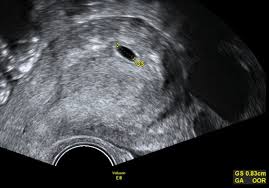

Besonderheiten beim Ultraschall in der 8SSW In der 8Schwangerschaftswoche ist der Kopf noch größer als der gesamte Körper des Embryos. In Ultraschall ist immernoch keine fruchthöhle zu sehen. Das baby ist in der 8 woche 2-3 cm groß und geschlecht wird man sicherlich nicht erkennen können.

Alle inneren Organe sind angelegt und unter dem Gaumen bilden sich die Zahnanlagen. Schwangerschaftswoche ist Ihre erste Vorsorgeuntersuchung fällig. Der Dottersack ist ein wenig beachteter Nebenbefund beim Ultraschall in der Frühschwangerschaft. Bei der ersten von insgesamt 3 Ultraschall-Untersuchungen wird ein Bild des Embryos aufgenommen. Ultraschall beim führenden Marktplatz für Gebrauchtmaschinen kaufe. Er hat jetzt winzige Hände und Füße wobei sich die oberen Extremitäten etwas schneller entwickeln als. Woche ist aus dem mikroskopisch kleinen Zellklümpchen ein 9 bis 16 Millimeter großer Minimensch geworden. Die Ellbogen nehmen Form an und die Entwicklung der Finger beginnt an den Beinen sind Ansätze der Füße und sogar schon Zehen erkennbar. Da meine fa am Anfang der ss in Urlaub war bin ich parallel.

Ultraschall über die bauchdecke wird viel später gemacht weil man sonst gar nichts erkennen kann. Wenn ich heute nicht gegangen wäre wäre alles okey. Diese gingen schnell vorbei. Der Embryo in der 8. 8 SSw Ultraschall was sieht man. Woche ist aus dem mikroskopisch kleinen Zellklümpchen ein 9 bis 16 Millimeter großer Minimensch geworden. Schwangerschaftswoche ist Ihre erste Vorsorgeuntersuchung fällig.